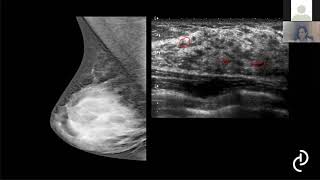

ressonância Oi aqui é um exemplo um casinho que eu trouxe de uma paciente que fez a ressonância pressa e painel e código que Peniel onde a gente vê que eu tomou regrediu na ressonância e eu trouxe para nós para isso que a reta não quer considerado o melhor método para avaliação da resposta terapêutica e esta estimado doença residual tratamento isso é um trabalho de 2.000 feio é a técnica do exame que a gente vai falar agora um pouquinho sobre o exame enfim utilizo que o aparelho aparelho de Alto campo magnético Campo a partir de 1,5

parente mas já consegui ver ele já consegui ver a forma as bordas a gente vai falar com alguns tipos de lesões que a gente tem e é para isso a gente usa o contraste é para isso a gente usa aí sequência dinâmica realiza-se uma sequência antes que a pré e depois seguido de três a cinco consequências totalizando de 47 minutos o e aqueles tem um exemplo de como funciona o estudo dinâmico Então a primeira imagem aqui do lado esquerdo é o P1 pré-contraste e aqui eu tenho de 1 a 4 que é como eu faço

contraste EA fazendo imagens sequenciais ao longo do tempo então primeira fase segunda fase terceira fase quarta fase atualizando aí eu não digo nem um minuto dois minutos porque às vezes dá mais do que um minuto uma fase então não gosto de falar um minuto porque vai até cinco negócio Enfim então primeira fase segunda fase terceira fase e papel a UNIP é uma reconstrução ele faz uma reconstrução volumétrica da sequência dinâmica eles ficam tem uma mapinha 3B a gente tem como ter uma noção geral a gente pode ver aqui na imagem do lado direito a gente